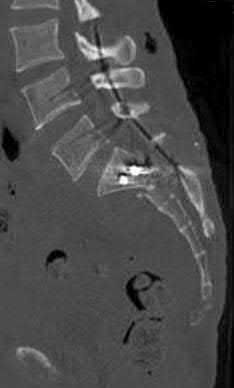

Question 6:

During a primary posterior-stabilized total knee arthroplasty, the surgeon assesses the flexion and extension gaps. The knee is found to be tight in both extension and flexion. Which of the following surgical adjustments is the most appropriate next step?

Correct Answer: Resect more proximal tibia

Explanation:

In gap balancing for total knee arthroplasty, the proximal tibial cut affects both the flexion and extension gaps equally. If the knee is symmetrically tight in both flexion and extension, resecting more proximal tibia (or using a thinner tibial polyethylene insert) will increase both gaps equally. Resecting more distal femur would only loosen the extension gap. Changing the femoral size primarily affects the flexion gap (downsizing loosens flexion; upsizing tightens flexion).